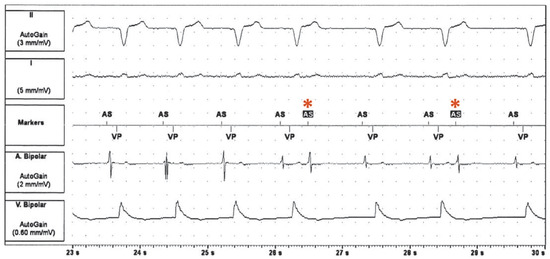

The tracing in Figure 1 shows a tachycardia with a CL of 500 ms and a 1:1 AV conduction. The tachycardia starts with a prematurely sensed atrial event (third atrial event on the tracing, marked * in Figure 2) and the tachycardia is tracked to the ventricle with an AV delay of 240 ms. During tachycardia, there is double ventricular farfield oversensing in the atrium. The first additional signal on the atrial channel, marked with a blue up-arrow in Figure 2, falls into the postventricular atrial blanking period (PVAB) and represents a farfield signal from the ventricular paced beat. The second oversensed signal (marked with a red down-arrow in Figure 2) is probably oversensing of the end of the QRS complex; T-wave oversensing is unlikely because it occurred even before the T-wave. This atrial signal falls into the postventricular atrial refractory period (PVARP).

The differential diagnosis of the tachycardia at this point is an atrial tachycardia conducted to the ventricles by tracking of the pacemaker, or an endless-loop reciprocating pacemaker-mediated tachycardia (PMT) due to retrograde conduction of ventricular paced beats that are sensed in the atrium after the PVARP. The end of the tachycardia contains the solution to this: after seven beats, the tachycardia terminates with an atrial beat that is no longer tracked to the ventricle (marked § in Figure 2). This makes atrial tachycardia highly unlikely, as one would have to assume simultaneous termination of an atrial burst and loss of ventricular tracking. The mechanism therefore is an endless-loop reciprocating pacemaker-mediated tachycardia.

Figure 2. Tachycardia observed during routine pacemaker interrogation with signs of explanation of the tachycardia mechanism. * The first beat of PMT. § The last beat of tachycardia, which is no longer tracked to the ventricle due to activation of the automode switch. Blue ↑ represents a farfield signal from the ventricular paced beat and falls into the postventricular atrial blanking period (PVAB). Red ↓ marks a second oversensed signal on the atrial channel (likely the end of QRS complex) which falls into the postventricular atrial refractory period (PVARP). AP = atrial paced event; AMS = automated mode switch; AS = atrial sensed event; AS = atrial sensed event in the postventricular atrial refractory period (PVARP); VP = ventricular paced event.